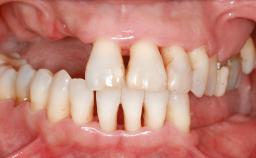

Guided Bone Regeneration (GBR) with a Particulated Autologous Graft and a ePTFE-Reinforced Membrane for Vertical Augmentation of a Single-Tooth Edentulous Space in the Esthetic Zone

A 47-year-old Caucasian woman with a single-tooth edentulous space at the site of the left maxillary canine was referred for treatment. She had undergone traumatic extraction of this impacted canine several months before referral. Her chief complaint was the dissatisfying appearance of her smile. The patient desired a stable and esthetic rehabilitation of the site. Her dental history showed no evidence of periodontal disease or bruxism. She had no systemic diseases, was not taking any medications, and did not smoke. The extraoral examination revealed a high lip line and an inadequate soft-tissue volume at the defective canine site. Large black triangles were visible between the canine and its adjacent teeth.